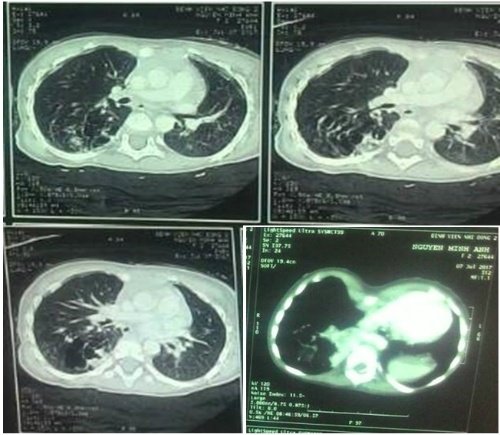

Bé gái có \'phổi biệt trí\'

<strong>Bệnh viện Nhi đồng 2 lần đầu phẫu thuật nội soi lồng ngực cho bé gái hai tuổi, cắt bỏ thùy dưới phổi phải chứa mô phổi biệt trí.</strong><br />